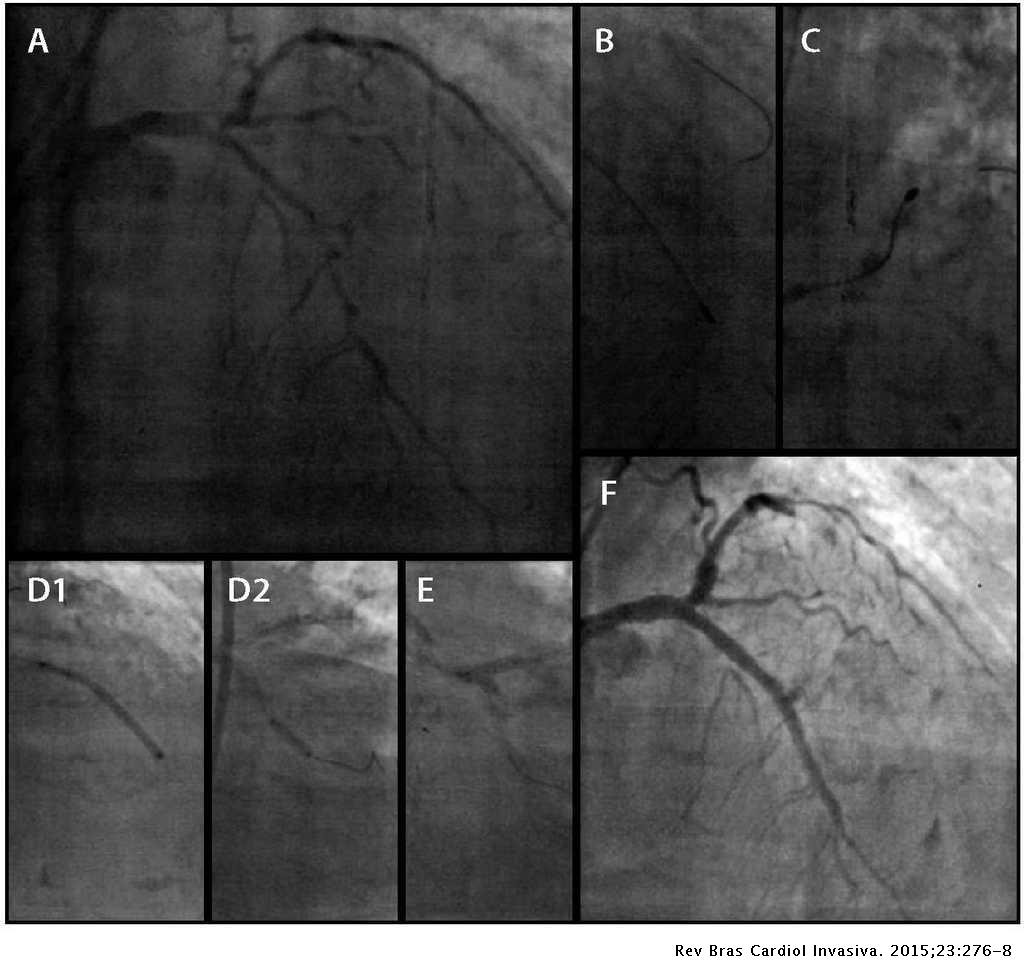

Acute coronary syndrome managment